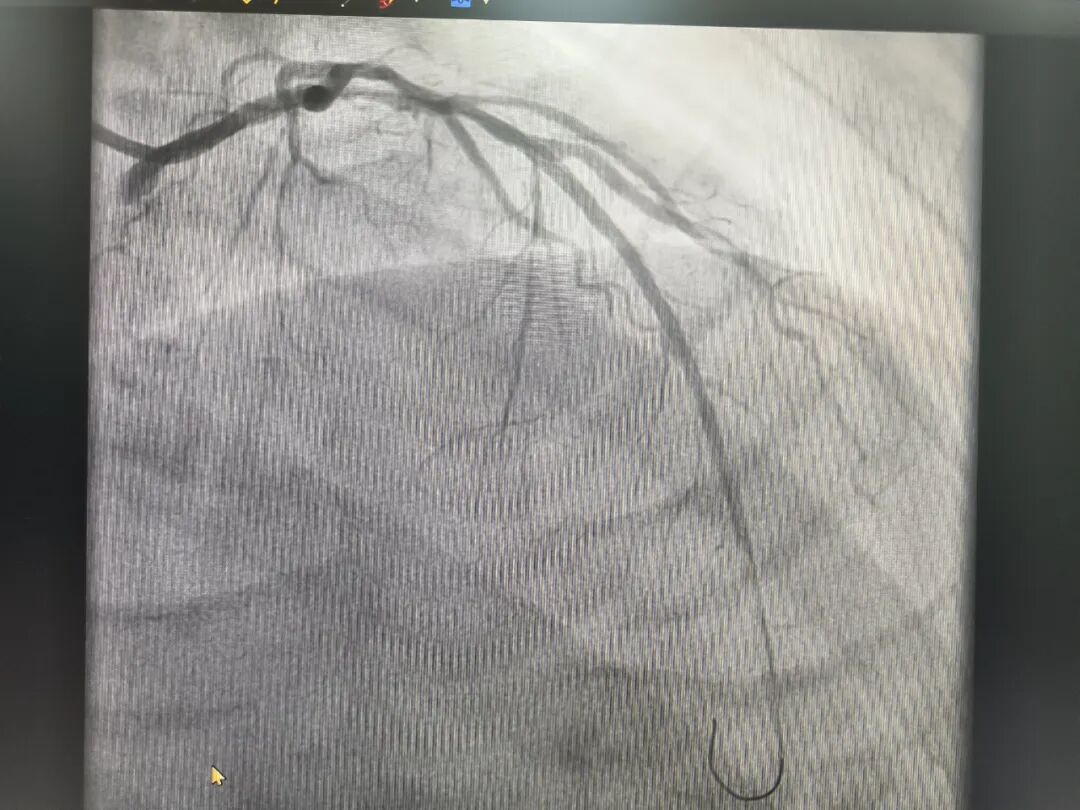

11月7日凌晨,78岁的陈大爷由于“胸痛,胸闷症状持续5天”至医院急诊科检查,值班医生在询问病史和完善相关检查后,与心内科联合会诊,诊断为急性心肌梗死。经过介入中心团队历时不到1小时的急诊冠脉支架手术,堵塞的血管被成功开通,患者转危为安。

对于这位急性心梗高龄患者,医院充分发挥介入手术室专科优势,成功为急性心肌梗死患者就诊开辟了绿色“生命通道”,心内科、急诊科等各个流程的医护人员相互配合,共同建立协同救治体系,在接诊、检查、治疗、手术及住院等各个环节上实施了快捷有效的急救措施,让“以患者为中心”的初心落到实处。